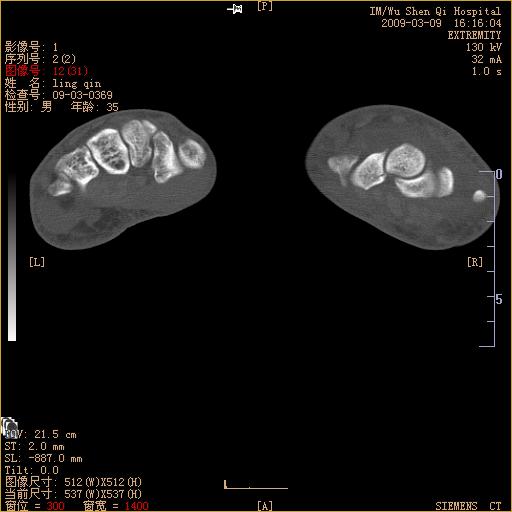

标题: CT18570:右手外伤10余天

请上传x线平片。舟状骨骨折可能大。

腕部有骨折、脱位,骨科面对ct片如何采取措施?三维一下。

请上传x线平片,腕骨多骨骨折

舟状骨骨折。

左侧舟骨及桡骨茎突骨折,第一掌骨基底部好像也有骨折,建议上传平片